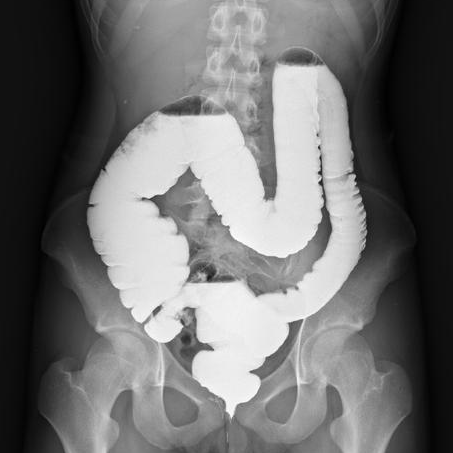

3、钡餐造影:

喝一杯“奶茶”(含钡造影剂),

X光下肠道轮廓清晰如地图,鼓包无所遁形。